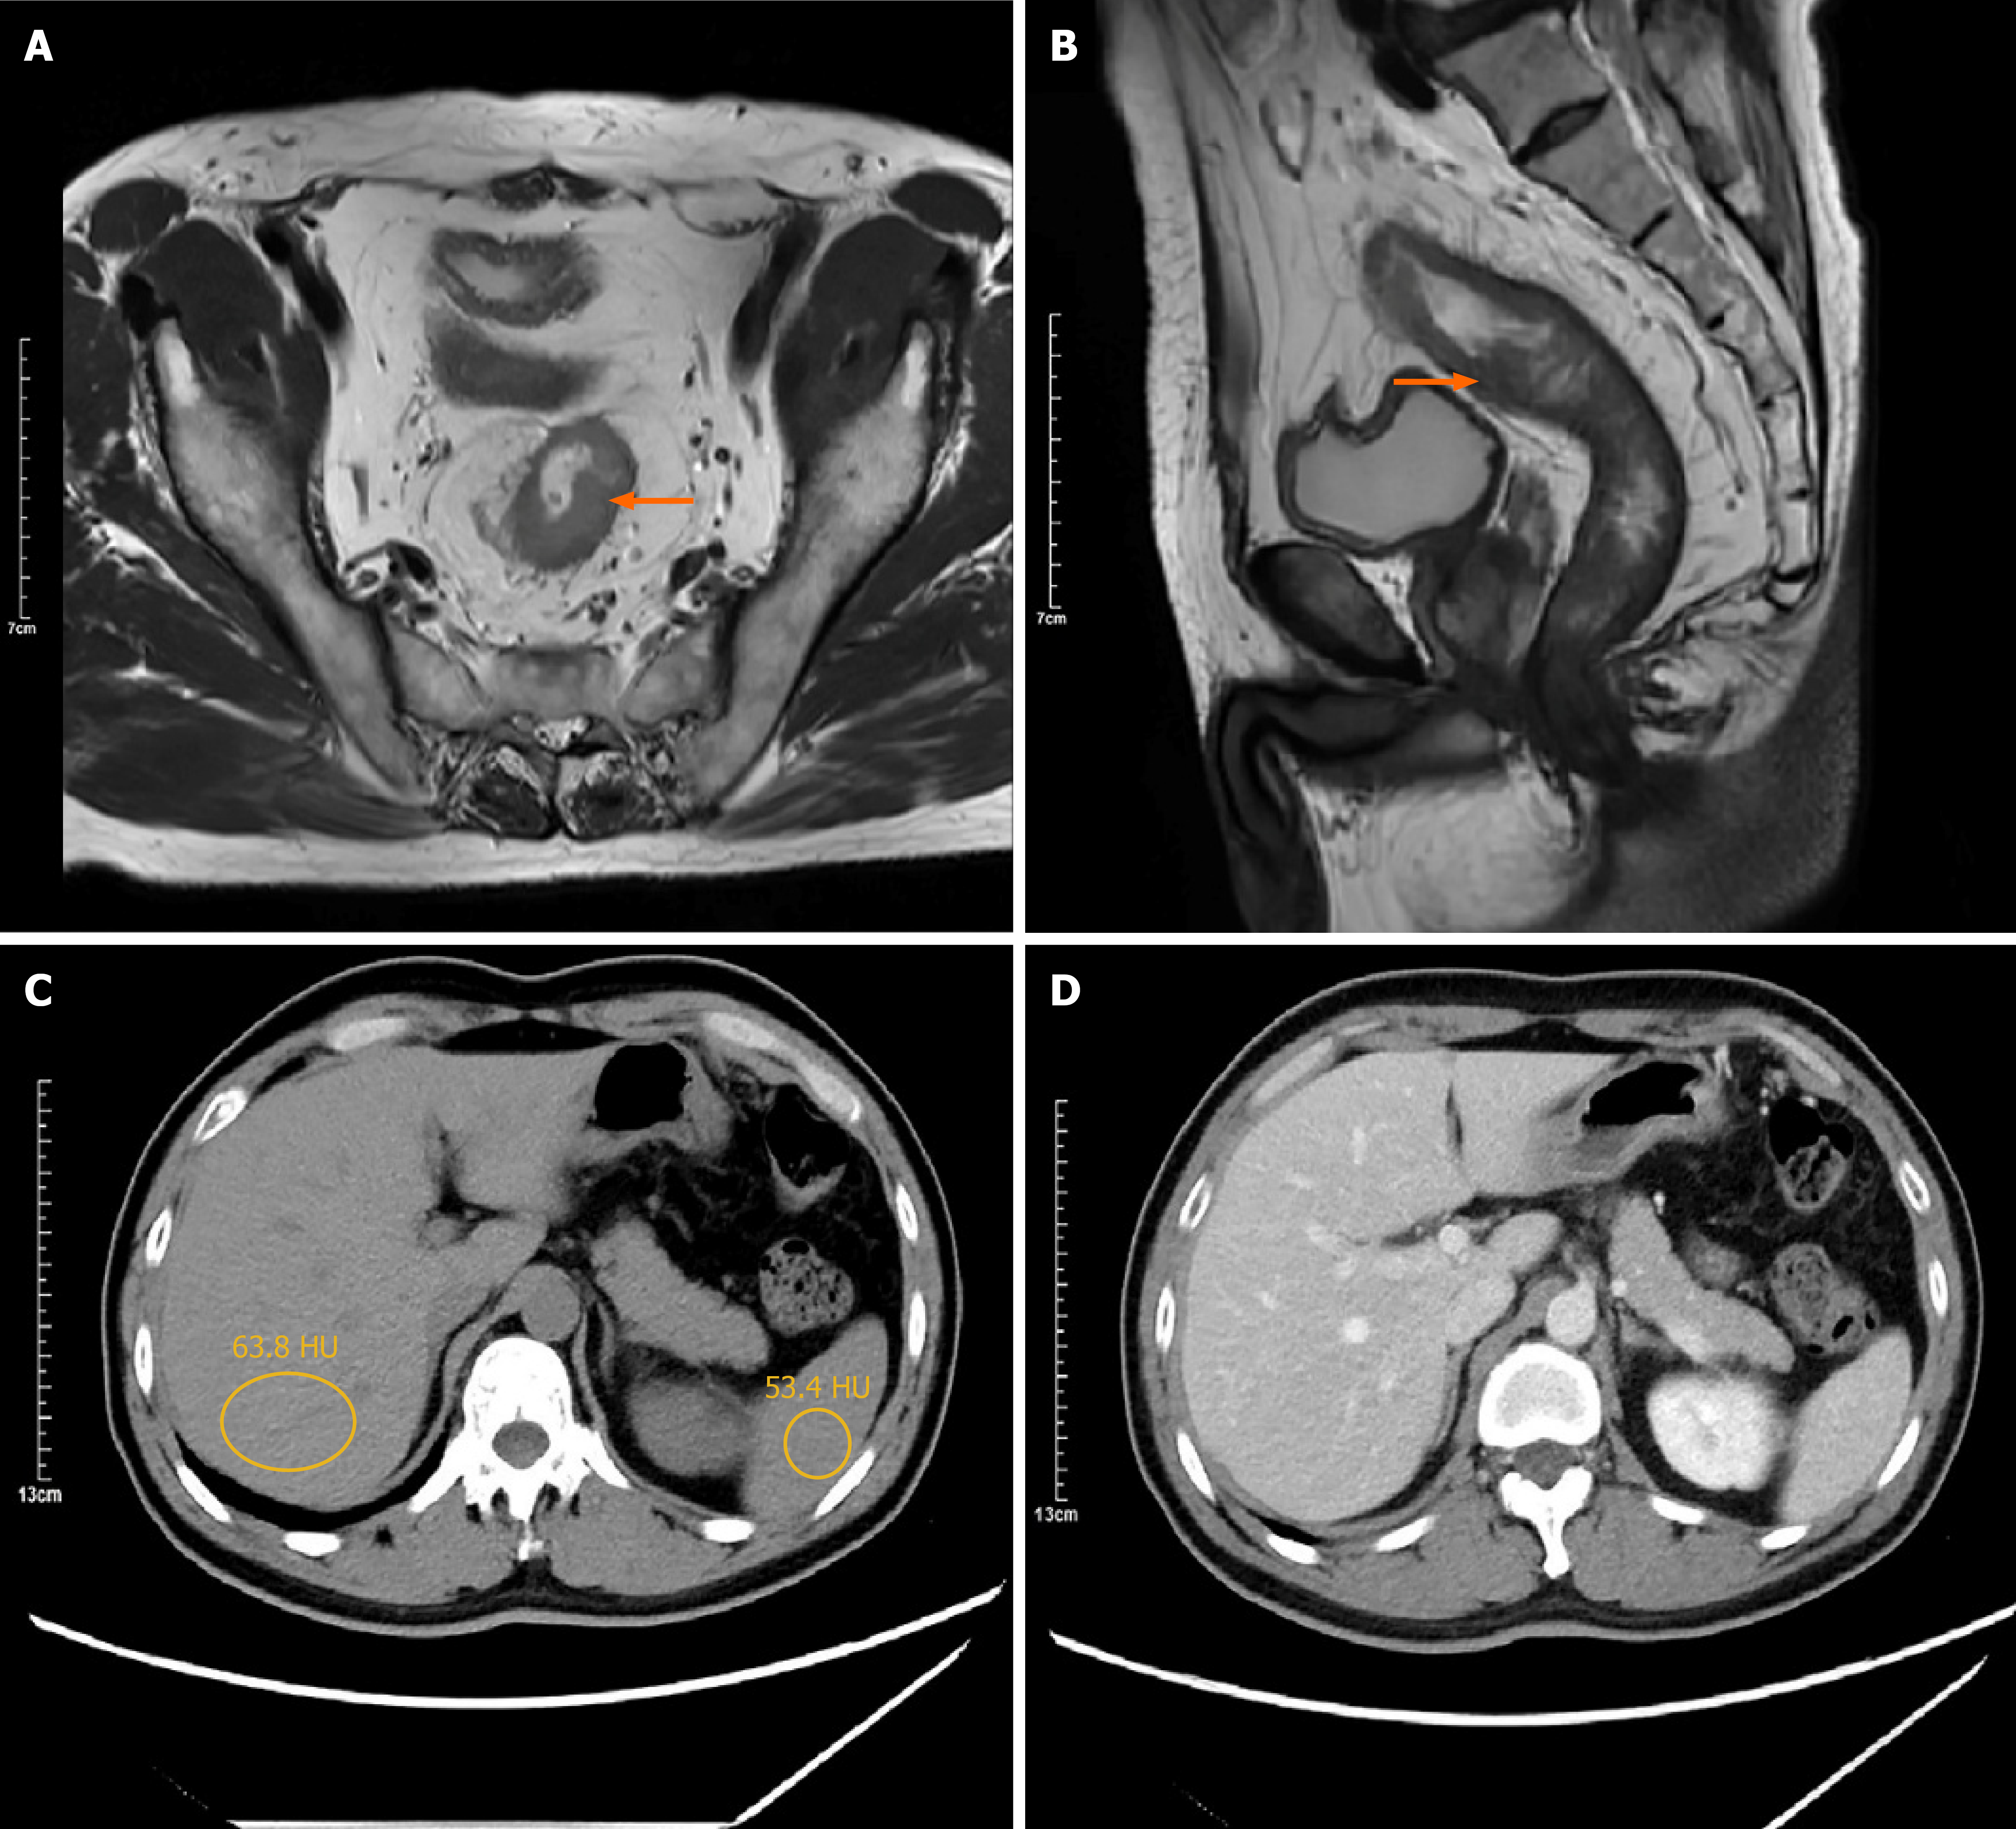

Colonoscopy revealed a 3.5-cm ulcerated, circumferential mass with irregular borders, located approximately 7 cm from the anal verge, consistent with features of malignancy. Histopathological analysis of biopsy specimens confirmed a moderately differentiated adenocarcinoma. Preoperative contrast-enhanced CT of the chest and abdomen demonstrated localized thickening of the rectal wall, without evidence of distant metastasis, including the liver and lungs. Pelvic magnetic resonance imaging identified a mid-rectal lesion with a negative circumferential resection margin (CRM) and no pelvic lateral lymphadenopathy (Figure 1). Baseline unenhanced abdominal CT showed no evidence of hepatic steatosis: Mean hepatic attenuation was 63.8 HU and the liver-to-spleen attenuation difference was 10.4 HU; both well within the normal range. Follow-up unenhanced CT at 6 months and 9 months after surgery revealed newly developed diffuse hepatic steatosis, with mean hepatic attenuation dropping to 27.4 HU and 20.6 HU, respectively, while splenic attenuation remained stable at 45.2 HU and 46.1 HU. After ileostomy reversal, serial CT scans at 3, 6, 9, and 18 months revealed progressive resolution of fatty liver, with complete normalization by 3 months and no recurrence thereafter (Figure 2). Postoperative pathology confirmed moderately differentiated adenocarcinoma with no lymph node metastasis (0/12), and the pathological stage was pT3N0M0. Both the CRM and stapler resection margins were negative.

Figure 2

Figure 2 Abdominal computed tomography scans after the first procedure. A-C: Scans obtained at 3, 6, and 9 months postoperatively, respectively (the circle: Hepatic/splenic attenuation in HU: A: 63.8/53.4; B: 27.4/45.2; C: 20.6/46.1).

NAFLD is a spectrum of liver disease characterized by excess hepatic fat accumulation in the absence of significant alcohol intake or secondary causes. Its prevalence is increasing worldwide, with strong associations to obesity, insulin resistance, and dyslipidemia[2,3]. The central pathogenic mechanisms of NAFLD involve overnutrition and insulin resistance, which lead to increased de novo lipogenesis, impaired lipid oxidation, and inflammatory responses in hepatocytes[4,16]. While most cases of NAFLD are associated with classical metabolic syndrome, our case illustrates a distinct etiology - transient enterohepatic hormonal dysregulation triggered by loop ileostomy. Several features in this patient support this hypothesis. First, although CT has limited sensitivity (46%-72%) for detecting early or mild steatosis[17], baseline abdominal CT scans showed no signs of hepatic steatosis with liver attenuation measuring > 60 HU and a liver-to-spleen attenuation difference > 10 HU (Figure 1). However, follow-up CT imaging at 6 months and 9 months postoperatively demonstrated new-onset diffuse hepatic steatosis with liver attenuation < 40 HU and a liver-to-spleen attenuation ratio of < 0.8, meeting the diagnostic criteria of hepatic steatosis[17] (Figure 3). The consistent progression and resolution pattern of hepatic steatosis on serial CT imaging, along with corresponding metabolic changes, support the temporal association with ileostomy status. Second, the steatosis reversed completely within 3 months of stoma closure, without lifestyle or pharmacological intervention. Third, the temporal trends in BMI, lipid profiles, and VAS-based appetite scores mirrored the radiologic course of hepatic steatosis. Finally, serial hormone assays revealed significant alterations in GLP-1 and PYY(3-36) concentrations before and after stoma closure, implicating a possible endocrine mechanism.